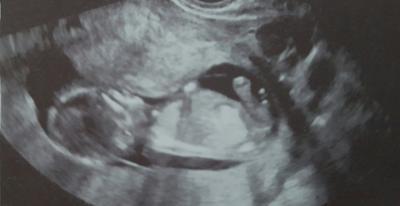

Was meint Ihr, Junge oder Mädchen? Ich bin ja so neugierig! Bin 13+1, aber so manch einer hat ja viel Ahnung von Nub-Theorien etc... Danke für Eure geschulten Blicke :-)

Bild zu Ein Outing?? - Schwanger - wer noch? Rund um die Schwangerschaft